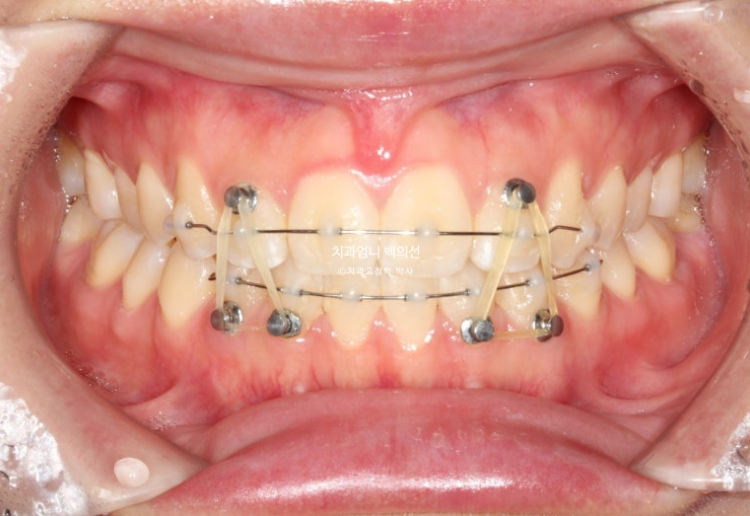

25.05

사용한 부분교정용 장치는 MTA 미니튜브 이고 고무줄 처방이 함께 들어갔습니다.

윗니가 아랫니를 앞에서 안정적으로 덮게 만들려면 아래 앞니에 치간삭제가 소량 필요합니다.